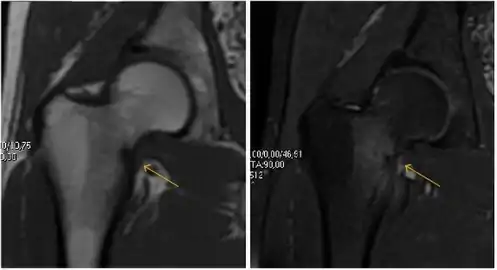

Most of the angles and measurements described in the plain radiograph section can be accurately reproduced on MRI. In addition, the superiority of MRI resolution with intra-articular contrast allows detection of labral and chondral abnormalities that may influence the choice of medical, percutaneous, or surgical management (Figure 9).[1]

Figure 9:

Sagittal T1 weighted image showing anterosuperior labral tear.[1]

Sagittal T1 weighted image showing chondral lesion.[1]

MRI has been shown to have 100% sensitivity and specificity in prospective studies of occult hip fractures. These fractures were diagnosed by bone marrow edema and a low signal fracture line, mainly on T1 or T2 weighted images (Figure 10).[1]

Figure 10:

Stress femoral neck fracture in a young athlete barely visible in X-ray film as a sclerotic line (arrow)[1]

In this case, Tc 99 scintigraphy shows a band of uptake[1]

Furthermore, T1 (left) and DP fat saturated (right) weighted MR images showed the fracture line and a pattern of edema.[1]